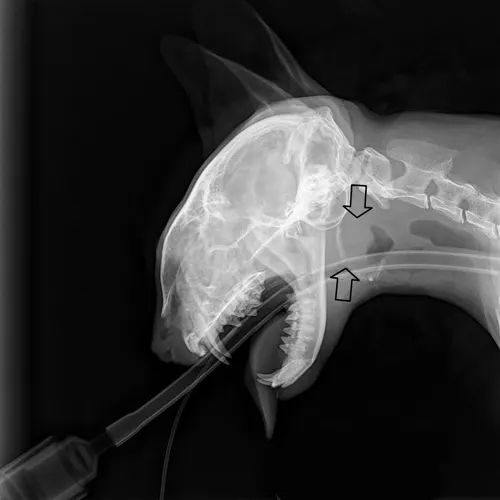

Chest radiography can rule out lower respiratory and metastatic disease (if malignancy is suspected). Skull radiographs —including open-mouth, lateral, lateral oblique (left and right), and ventrodorsal views—are also obtained (Figures 2 and 3). False-negative results are common with bulla radiographs. Computer tomography (CT) is sensitive for the detection of middle ear involvement.

FIGURE 2 Open-mouth radiograph of a cat with inflammatory polyps. Note the thickened bulla (arrow) compared with the contralateral normal bulla.